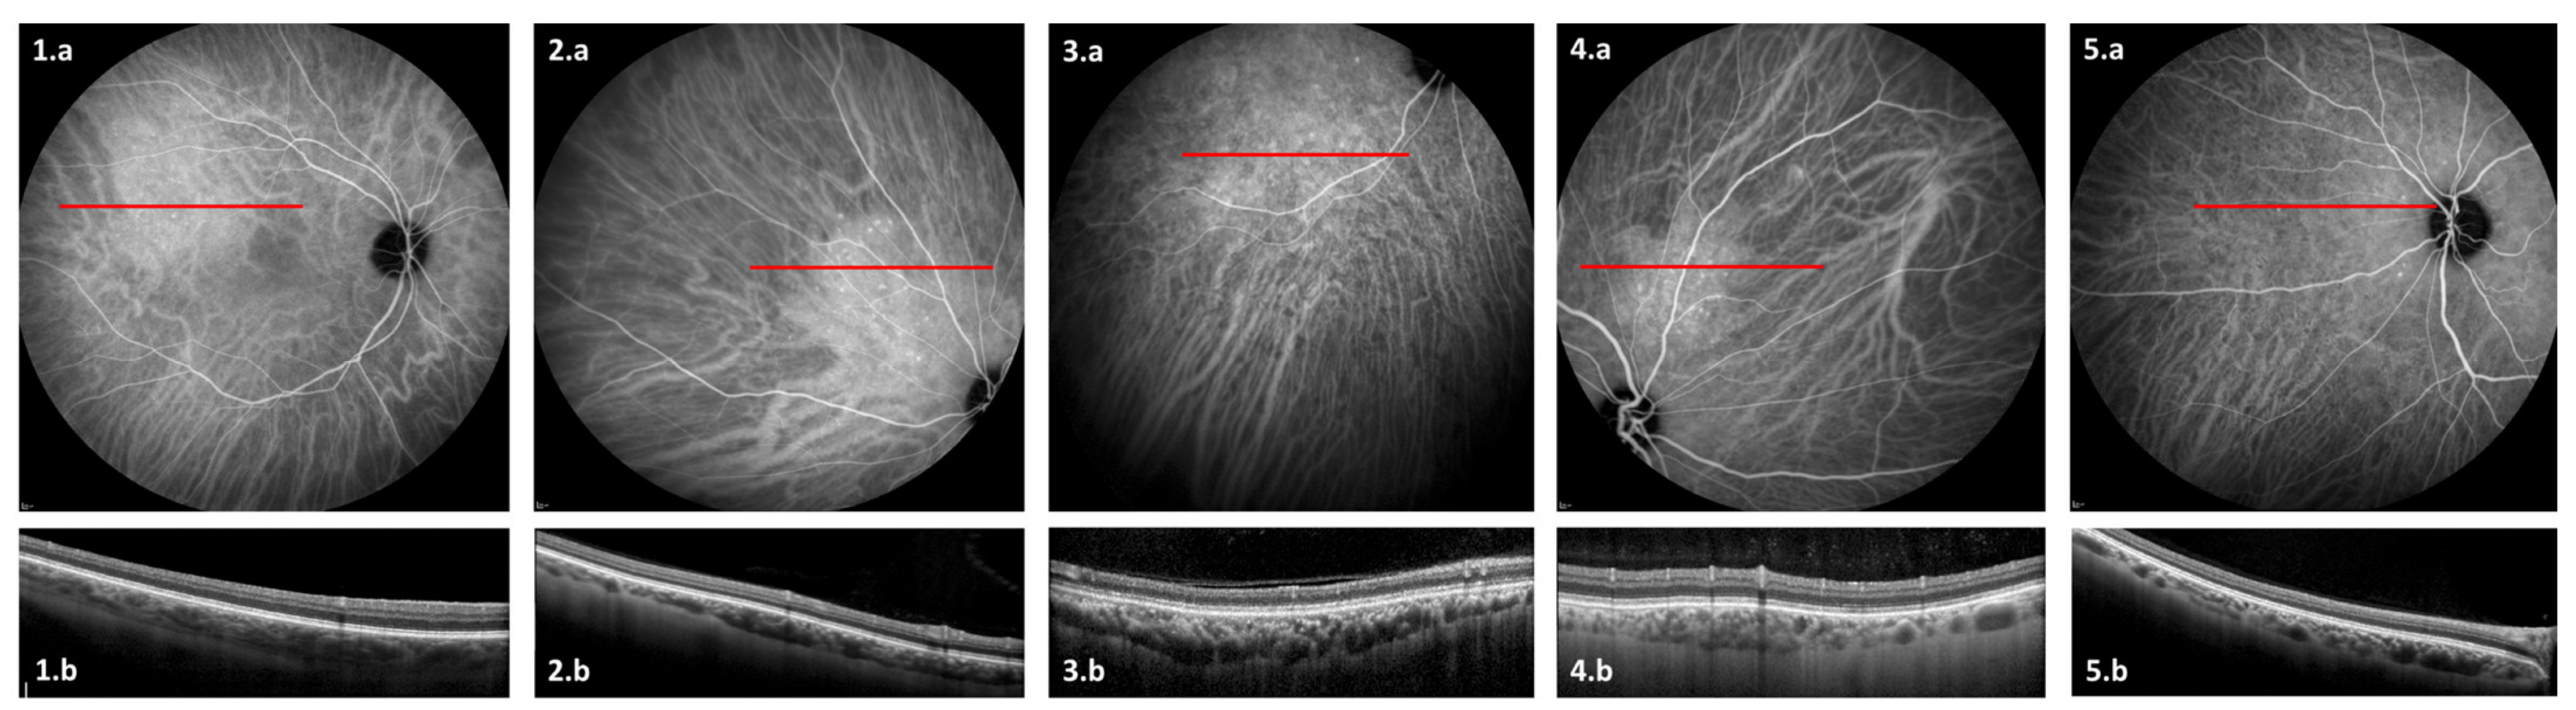

3.2. OCT Findings

3.3. ICGA Findings

| Vessel leakage and/or staining Hypofluorescent spots Pintpoint leakage Intervortex shunts “Hemangioma-like” lesion | 20 (71%) 19 (68%) 15 (54%) 10 (36%) 5 (18%) |

| OCT anomalies | Number of eyes (%) |

| Pachyvessels Focal choroidal thickening Caverns | 25 (89%) 7 (25%) 6 (21%) |

| Choroidal thickness in μm (mean ± SD (range)) | 265.3 ± 73.3 (67–432) |

| Central macular thickness in μm (mean ± SD (range)) | 273.4 ± 26.7 (183–320) |